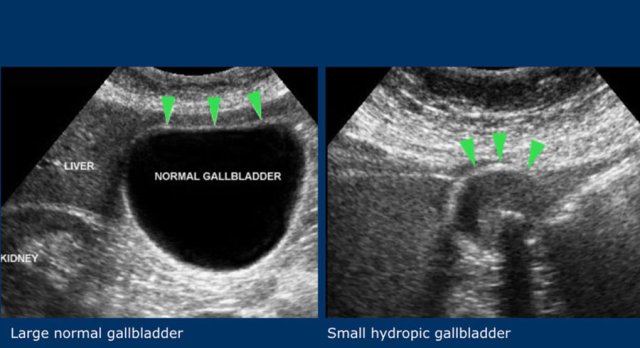

The third sign is a large transverse diameter of the gallbladder.

This is not a very reliable sign, since gallbladder diameters have a wide range.

A 2.5 cm gallbladder can be hydropic and a 5 cm diameter gallbladder can be normal (fig).

Therefore, non-compressibility and preservation of the round shape during compression, remain the US hallmarks of hydrops.